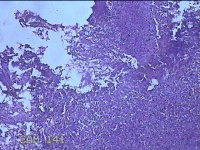

右侧窦腔内容物

性别

男

年龄

49岁

临床诊断

1.慢性鼻窦炎 2.鼻中隔偏曲 3.变应性鼻炎

一般病史

鼻塞、脓涕2月,加重伴涕中带血1周。

标本名称

大体所见

灰白暗红色不规则碎组织1.5x1.3x0.3cm一堆。

图2